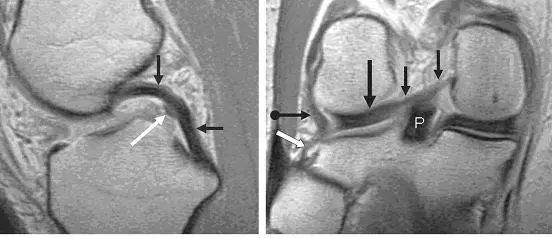

左图:经过后交叉韧带的矢状面,显示连续均质低信号的后交叉韧带(黑色箭头),其前方是半月板股骨前韧带(Humphry 韧带,白色箭头)。右图:冠状位片显示半月板股骨后韧带(Wrisberg 韧带,黑色短箭头不带圆点)从外侧半月板后角(黑色长直箭头)连接到股骨内侧髁外面。同时可见腘腓韧带(白色箭头)从腓骨头到腘肌腱(黑色短圆箭头),P 为后交叉韧带。